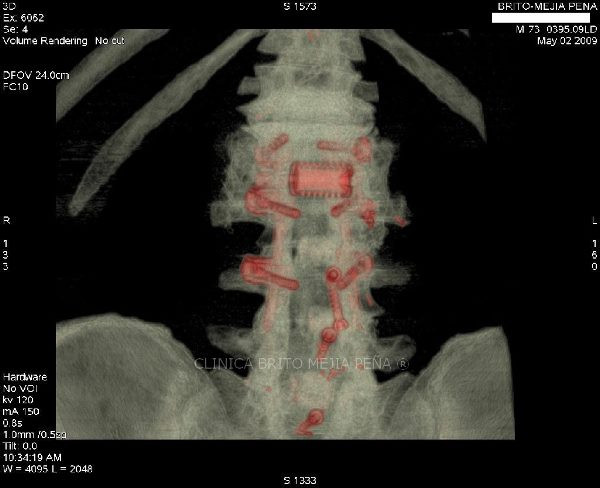

Instrumentalización columna 3D

Instrumentalización columna ósea